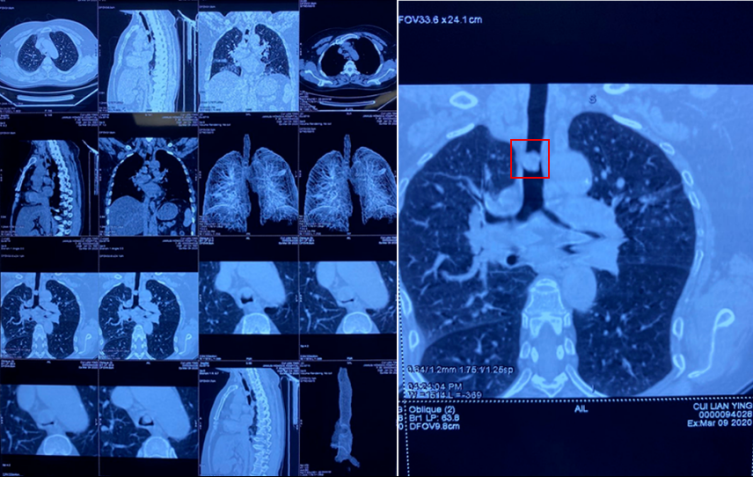

患者崔某,女,59歲,長(zhǎng)期因胸悶氣短,呼吸困難4個(gè)月左右,多次輾轉(zhuǎn)于省內(nèi)各大醫(yī)院就診,因腫瘤位置特殊隱蔽少見,長(zhǎng)期造成漏診誤診,總是以肺氣腫,支氣管炎接受治療,病情逐漸加重。尤其是近一個(gè)月,病人呼吸困難持續(xù)加重,端坐呼吸,日夜不能平臥,口唇紫紺,生命危在旦夕。經(jīng)人介紹來到了佳木斯大學(xué)宏大醫(yī)院胸外科就診,入院后胸部CT檢查發(fā)現(xiàn)主氣管腫瘤,阻塞氣管腔85%以上,病人出現(xiàn)窒息,隨時(shí)可能呼吸障礙死亡。

由于病人氣道巨大腫瘤阻塞,呼吸困難,吸氧緩解效果不良,只能依賴呼吸興奮劑等藥物緩解。術(shù)前胸外科手術(shù)團(tuán)隊(duì)聯(lián)合麻醉科左會(huì)明主任、手術(shù)室孫蘭英主任以及相關(guān)科室,詳細(xì)制定手術(shù)方案和應(yīng)急預(yù)案,決定采取超細(xì)氣管插管,解決手術(shù)麻醉通氣問題,打破常規(guī)采取雙麻醉機(jī)和雙通氣途徑,確保手術(shù)麻醉安全。術(shù)式?jīng)Q定為主氣管腫瘤切除氣道吻合成形重建術(shù)。對(duì)于手術(shù)風(fēng)險(xiǎn),病人及家屬對(duì)佳木斯大學(xué)宏大醫(yī)院及手術(shù)支持團(tuán)隊(duì)給予了充分的信任,并以生命相依托,相信手術(shù)定會(huì)成功。帶著病人及家屬的重托,手術(shù)團(tuán)隊(duì)經(jīng)過近4個(gè)小時(shí)努力,成功實(shí)施開胸手術(shù)切除胸段主氣管腫瘤,腫瘤大2.8*1.6*1.5CM,幾乎完全阻塞氣道。術(shù)中病理診斷為少見的氣管惡性腫瘤——惡性淋巴瘤。氣管I期吻合成功,術(shù)后無漏氣及出血。術(shù)中曾經(jīng)歷了驚心動(dòng)魄的30秒低氧血癥期,心跳近乎停止,經(jīng)搶救轉(zhuǎn)危為安。